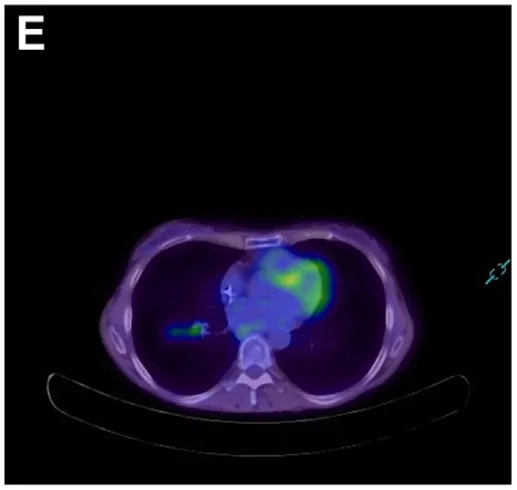

考虑到炎症性肠神经节炎的提示,遂行血清抗神经元抗体检测,结果显示抗神经元核抗体(ANNA)-1/Hu和SOX-1抗体阳性。复查氟代脱氧葡萄糖-PET扫描显示右肺下叶存在明显高代谢病灶,伴同侧纵隔淋巴结受累(图E)。